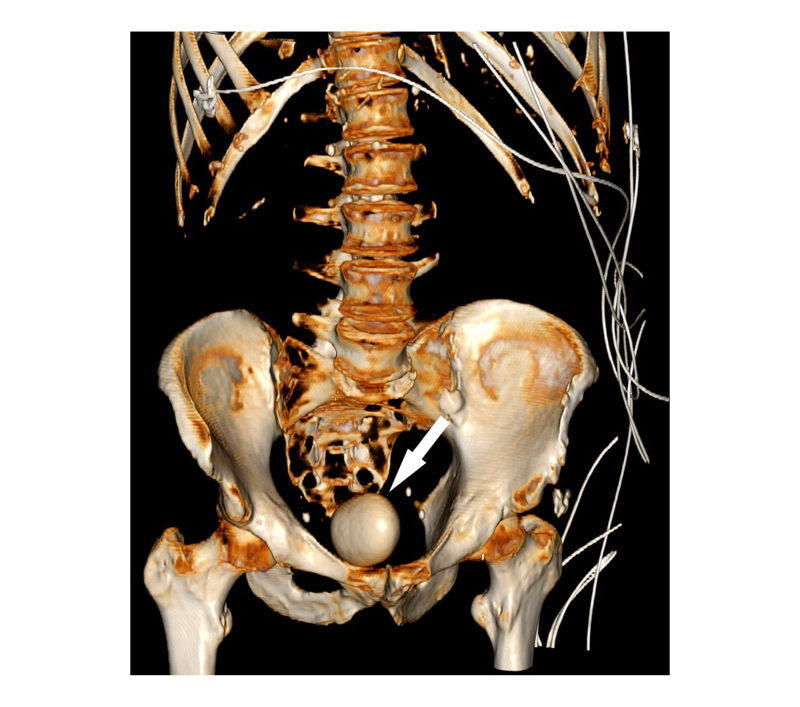

A new abdominal/pelvic CT scan showed a 6 cm bladder calculus, and mild left kidney pelviectasis (Figure 1B). A 3D CT reconstruction is shown in Figure 2. Creatinine was 138 µmol/L with a baseline of 120 µmol/L. White blood cell count was 10.9×109 /L and haemoglobin was 157 g/L. Urine culture had insignificant growth. Catheter placement with cystoscopy and guidewire failed as the balloon burst shortly after placement. On cystoscopy, the patient had evidence of a moderately obstructing prostate. There were no urethral abnormalities. The urothelium could not be visualised, as the stone was occupying the entire bladder space.

Figure 2: 3D CT reconstruction of bladder stone from 32 months after initial presentation.